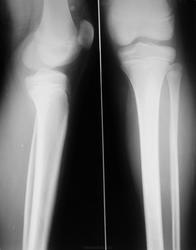

Кости голени + коленный сустав (Мальчика 12 лет сбила машина)

Мальчик, 12 лет, шел по пешеходному переходу на зеленый свет, его сбила машина..

Если боль в средней трети, то косой перелом ср/3 диафиза б/б кости практически без смещения. Если подозрение на артефакт, но есть клиника, то контактный снимок с диафрагмированием может помочь.

Косой перелом б/берцовой кости на границе с/3 и н/3 диафиза + перелом в/3 диафиза м/берцовой кости без смещения..

про малоберцовую кость соглашусь, перелом без смещения можно заподозрить, а вот в большеберцовой кости диафиз в норме (это артефакт на пленке).

Проксимальный эпифиз ББК не смущает ?

Артефакт очень подозрительный, я бы пересняла, но спорить не буду. В проксимальном отделе б/берцовой убедительных данных за повреждение не вижу. Важна клиника, зона роста не закрыта.

Малоберцовая сломана.

Предположим, что перелом диафиза большеберцовой кости есть (стрелка). Но где все видят перелом малоберцовой?

На вашем изображении увидел и перелом м/б. Есть костное тело в проекции верхнего заворота, возможно хондроматоз. Только вот вопрос : у детей он встречается?

Ну, что ж, дело судебное, посему - либо МСКТ, либо контрольный рентген через 7-10 дн. без гипса.

По поводу малоберцовой - травматологи тоже согласны, что скорее всего есть. тем более как раз на этом уровне огромная гематома была.